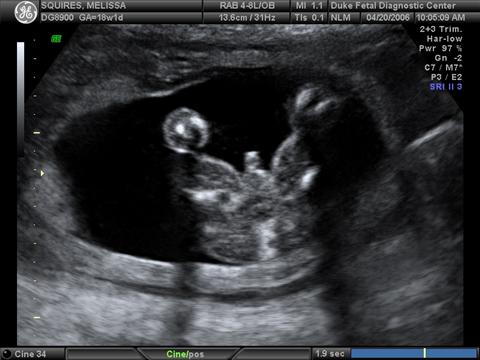

Pics from the 18 week sono...

He doesn't look as much of a skeleton that I thought he would!

1st pic profile pic of him yawning, 2nd pic is him in all of his glory, and the 3D pic. What do you think? Thanks! Image Attachment(s):

(I love the "in his glory" shot .. no denying that's a boy there!! )

Beautiful!!! And yep thats definitely a boy!!

wow all boy!! congrats, he looks great

Wow! There is no mistaking that's a boy